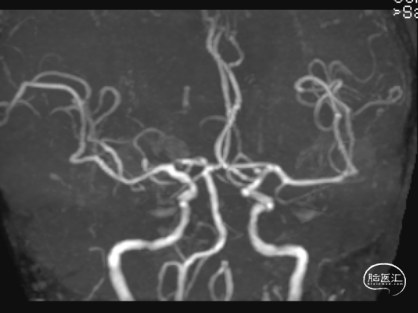

术后第5天,头晕症状完全消失,双上肢收缩压差8mmHg,NIHSS 0分。